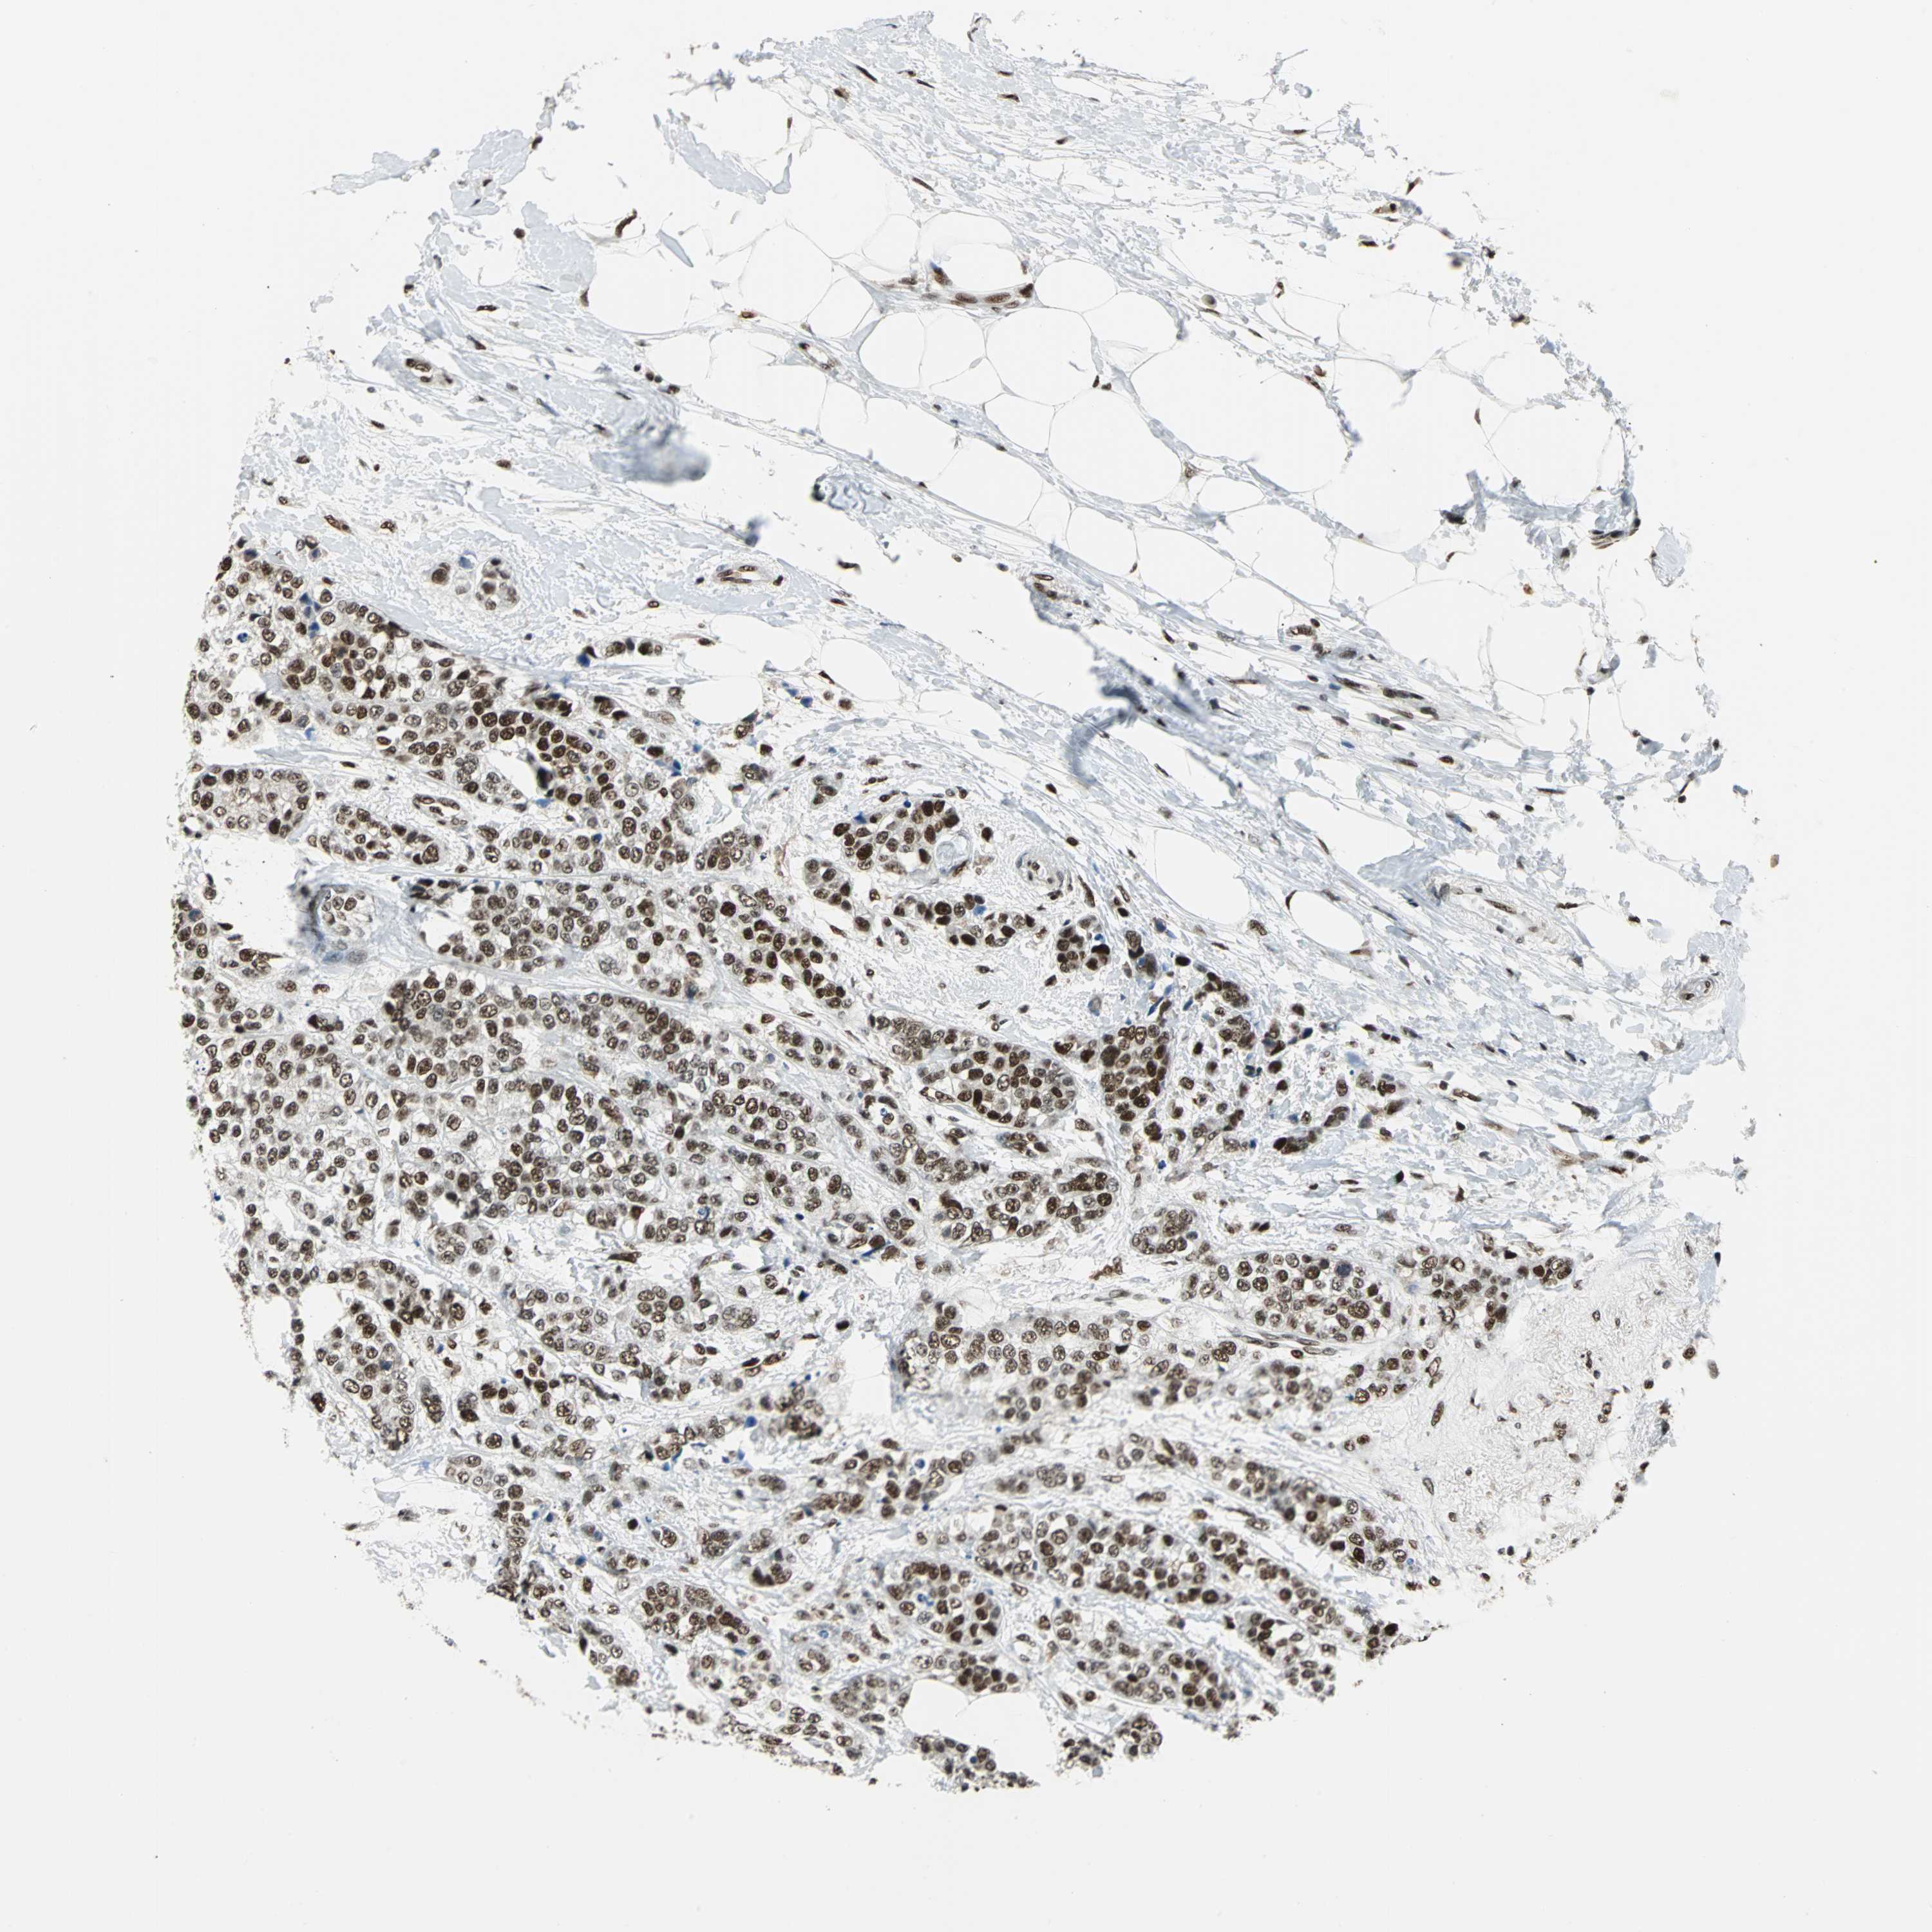

BRCA TCGA BRCA VALIDATION PROTEIN EXPRESSION

ANTIBODIES

AND

VALIDATION